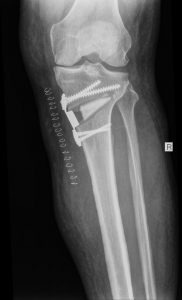

HIGH TIBIAL OSTEOTOMY

Some patients have degeneration of one compartment of the knee, but they are too young to have a total knee replacement. For them it makes sense to change the alignment of the leg so the weightbearing axis runs through the healthy compartment. This allows pain free mobilization for several years. A knee replacement can then be done when the patient is older.

BEFORE OPERATION

AFTER OPERATION